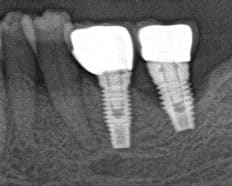

Voici la radio implants poses en 2007.

La radio ou tout va bien c'est 2009, et l'autre c'est aujourd'hui.

En bouche, asymptomatique, mais suppuration sulculaire presente. Pas de mobilite pour le moment.